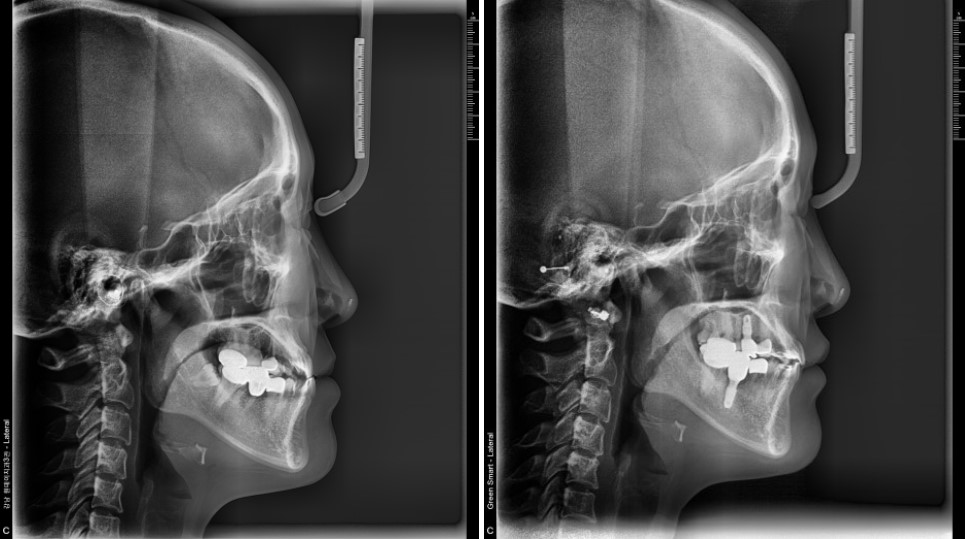

그렇다면 옆모습은 어떻게 변했을까요?

치료 전·후 옆모습 X-ray를 비교해 보면,

수술을 하지 않았음에도 턱과 입 주변의 라인이 부드럽게 개선된 것을 확인할 수 있습니다.

치료 전 입안 사진과 X-ray를 보면,

교합이 전반적으로 매우 불안정한 상태였고,

옆모습에서도 턱 라인이 거칠게 느껴지는 케이스였습니다.

옆모습 역시,

수술을 한 것처럼 드라마틱하게 변하는 것은 아니지만,

교합이 안정되면서 아랫입술이 자연스럽게 뒤로 들어가고,

얼굴 인상이 한결 편안해진 것을 확인할 수 있었습니다.